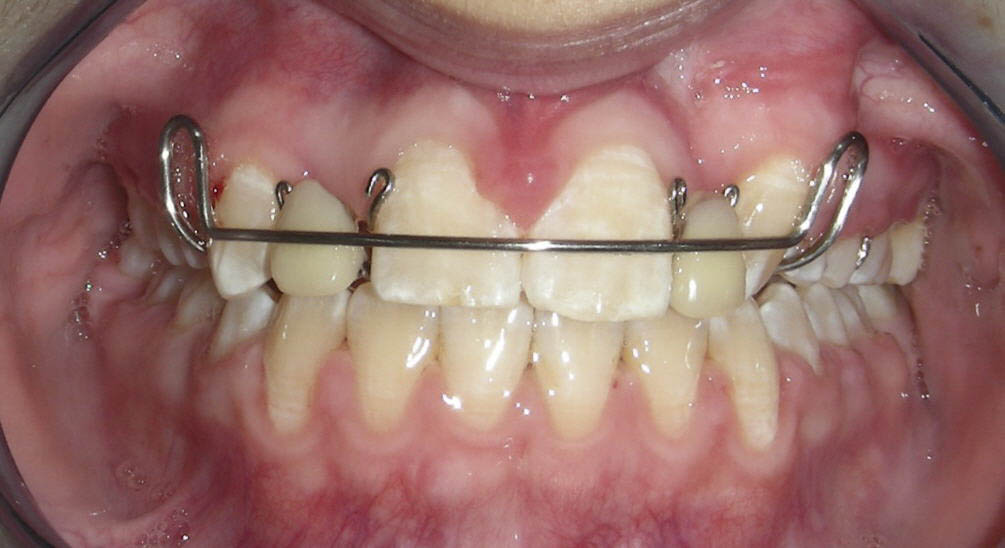

Prima fază a tratamentului s-a adresat corectării ocluziei inverse frontale. Dacă pacientul cooperează, atunci o placă cu prelungiri ocluzale şi croşete ”în deget” (finger spring) reprezintă o alternativă foarte eficientă şi relativ ieftină de corectare a ocluziei inverse. Dacă varianta aparatului mobil nu generează corectarea angrenajului invers, atunci se pot aplica aparate fixe. Astfel, în cazul de faţă, faza I a terapiei, ortodontică, a constat într-o placă cu prelungiri ocluzale şi cu croşete ”în deget” care cuprind incisivii centrali superiori, în vederea corectării ocluziei inverse. Incisivii laterali temporari superiori au fost extraşi pentru a asigura erupţia incisivilor centrali maxilari permanenţi. Molarii primi superior şi inferior de pe partea dreaptă au erupt într-un raport invers posterior, aşa încât au fost purtate elastice cross mai multe luni pentru a-l corecta.

Faza a II-a a debutat cu un aparat fix ortodontic 2×2, aplicat la nivelul primilor molari şi al incisivilor centrali maxilari, în vederea derotării primului molar drept. Ulterior, s-au aplicat aparate fixe pe întreaga arcadă, cu scopul de a controla erupţia dentară. Caninul stâng superior a fost descoperit chirurgical într-o fază timpurie de tratament şi a durat aproximativ 18 luni pentru a putea fi aliniat pe arcadă (fig. 5). Pacienta a purtat elastice de clasa a doua pe partea stângă pentru a tracţiona caninul în poziţie; cu toate acestea, acest dinte nu a ajuns niciodată în raportul de clasa I, neutral, dorit.